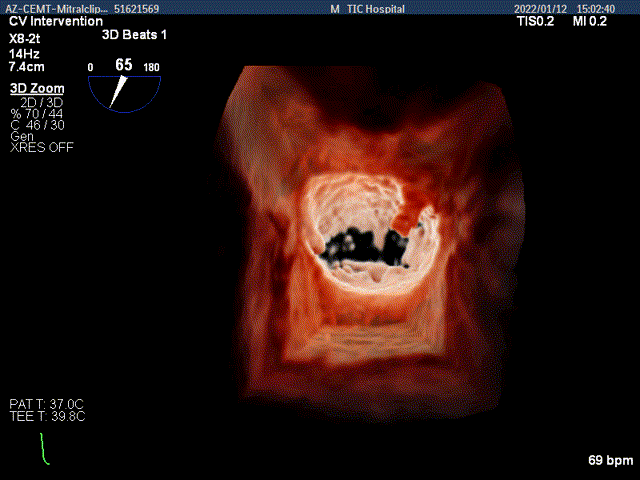

3D MV View:二尖瓣AC区为主(累及部分1区)脱垂并腱索断裂

3D-color MV view:大量返流,主要来源于AC区

TEE Bicom view:二尖瓣AC区为主(累及部分1区)脱垂并腱索断裂。

Color-view:大量返流,主要来源于AC区